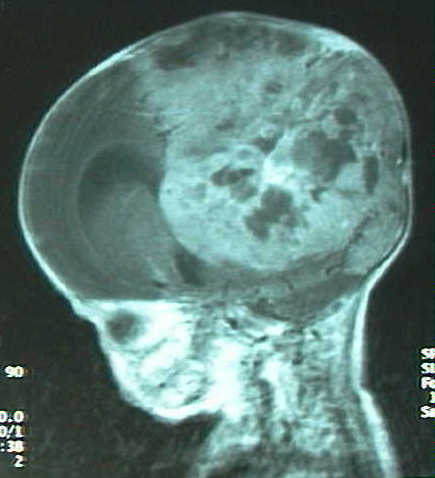

Figura 1 : Imagen por ecografía (a) y por Tomografía Computada con contraste (b). Se observa una gran masa tumoral ocupando la mayor parte del hemisferio izquierdo e hidrocefalia derecha.

En controles ecográficos y por tomografia computada posteriores (fig. 1a-b) se constata necrosis tumoral, dilatación de vena cava superior y shunt derecha-izquierda a nivel del ductus arteriosus; clínicamente se detecta proptosis izquierda, hipotensión, reborde hepático, e hiperbilirrubinemia que precisa fototerapia. Se practican estudios por Resonancia Magnética para estudio de extensión e intentar caracterizar la masa (fig 2a-c).